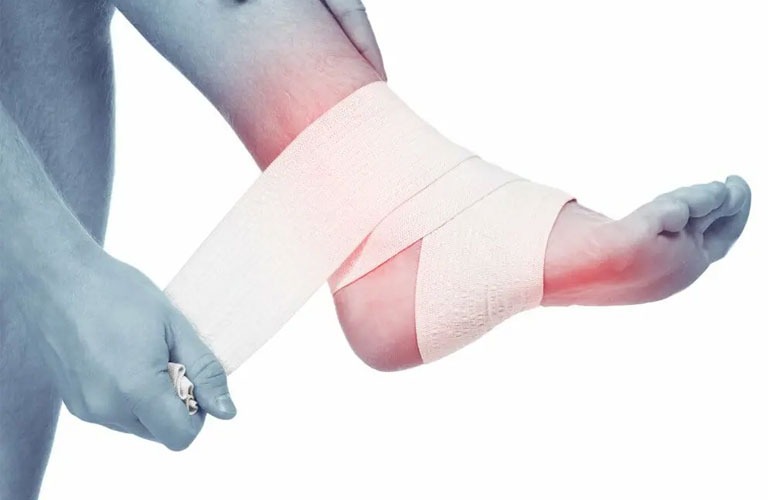

2, Sơ cứu bong gân:

Bong gân là tình trạng các dây chằng xung quanh khớp bị giãn quá mức, có thể dẫn đến rách một phần hoặc rách toàn bộ dây chằng dưới tác động của lực chấn thương.

Khi bị bong gân, người bệnh cần dừng cử động và thực hiện các cách sơ cứu sau trong vòng 48 giờ:

Nghỉ ngơi: Hạn chế hoàn toàn các cử động để vùng bị thương nghỉ ngơi đến khi giảm đau.

Chườm lạnh: Chườm lạnh vùng bị bong gân ngay lập tức, thực hiện 4 - 8 lần/ngày và khoảng 10 - 15 phút/lần. Cách này sẽ giúp giảm đau sưng. Sau khoảng 2 ngày chườm lạnh thì bạn hãy chuyển sang ngâm nước ấm.

Cố định khớp: Sử dụng loại băng vải có độ đàn hồi cao băng vùng bị bong gân khoảng 2 ngày, lưu ý không nên băng quá chặt. Cách này giúp giảm sưng.

Nâng cao vùng bị thương: Nâng hoặc kê cao vùng bị bong gân so với tim giảm tình trạng sưng phù.